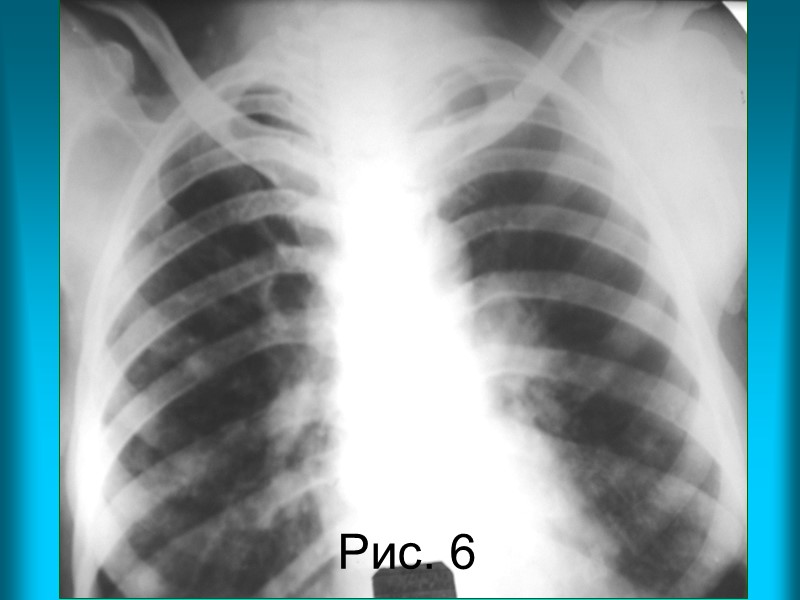

Н.С. Воротынцева. С.С. Гольев Рентгенопульмонология Пациентка М. 48л. Диагноз: метастазы рака правой молочной железы в легкие. Рис. 16. Рентгенограмма органов грудной полости в прямой проекции. Тень правой молочной железы отсутствует. Оба легочные поля понижены в прозрачности за счет диссеминированных очаговых теней слабой интенсивности. Легочный рисунок не виден за разновеликими очаговыми тенями. Корни легких расширены. Контур корня левого легкого полицикличный за счет увеличенных лимфатических узлов.

Н.С. Воротынцева. С.С. Гольев Рентгенопульмонология Рис. 6